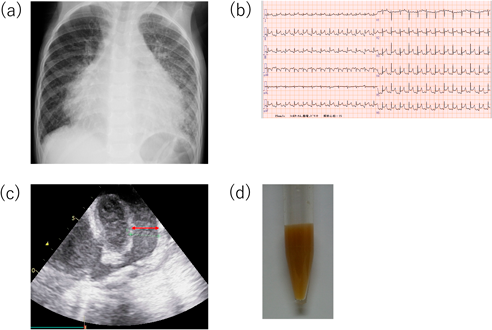

しかし,治療終了後も胸部X線で肺間質陰影の増強が改善せず,発症から3カ月後の胸部単純computed tomography(CT)検査で肺小葉間隔壁の肥厚を認めた(Fig. 2a).本人の自覚症状は特になく,肺線維化マーカーの上昇を認めず,心嚢液再貯留も認めなかったため,外来経過観察を継続した.外来経過観察中,下腿浮腫や肝腫大など右心不全症状は認めず,心臓超音波検査も繰り返し行われたが,心機能は良好で心嚢液の再貯留もなく,拡張障害も明らかでなかった.しかし,胸部X線所見は改善せず,発症後5年頃から徐々に易疲労感を認めるようになったため8歳時に胸部単純CT検査を再検したところ,肺小葉間隔壁の肥厚は悪化していた(Fig. 2b).心筋症の鑑別に心臓MRIを撮像し,心筋の肥厚や菲薄化は認めず遅延造影も陰性で心筋症は否定的であったが,心膜肥厚を認め(Fig. 2c),収縮性心膜炎が鑑別に挙がった.その精査のため,また心筋症の鑑別のため,9歳時に心臓カテーテル検査を行った.その時の圧データをTable 1に,右室圧曲線をFig. 3に示す.右室拡張末期圧の上昇を認めず,右室圧波形もdip and plateau型を示しておらず,収縮性心膜炎も否定的な所見であった.心筋生検も行ったが,錯綜配列などは認めず心筋症も否定された.

収縮性心膜炎は,心膜の肥厚が原因とされ,成人では4 mm以上の壁厚が肥厚と判定される13).心臓超音波検査における拡張障害や,心臓カテーテル検査における心内圧曲線でdip and plateauが特徴的とされる.dip and plateau波形は,ゼロ以下の拡張期下降から急峻な立ち上がりで拡張期plateauに続き,拡張期plateau圧は収縮期の3分の1を超えるとされている14).本症例は心膜肥厚を疑う所見を認め(Fig. 2),心臓超音波検査で拡張障害は明らかでなかったが,その時点ではGLA/GSD病は鑑別に挙がっておらず,病歴からも収縮性心膜炎の可能性が高いと考えられたため,心臓カテーテル検査を行った.しかし,心臓カテーテル検査でもdip and plateau型の心内圧曲線は認めず(Fig. 3),収縮性心膜炎は否定的であり,心筋生検も行ったが心筋症も否定された.